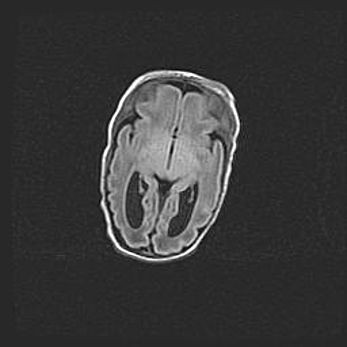

Неполная лизэнцефалия (пахигирия). Открытая гидроцефалия.

Возраст: 17 дней

Вес: 3110 г

Пол: мужской

Окружность головы: 33,5 см

Срок гестации: 35-36 недель

Лизэнцефалия—недоразвитие корковой пластинки и мозговых извилин в результате нарушения миграции нейронов коры. Поверхность мозговых полушарий гладкая. Микроскопически выявляется отсутствие нормальных слоев коры и скопление групп нейронов в подкорковом белом веществе.

Пахигирия—уменьшение числа вторичных извилин. В пораженном полушарии нервные клетки образуют толстый недифференцированный слой с неправильно расположенными нервными волокнами и группами гетеротопных клеток. Нервные клетки незрелые. Белое вещество истончено. При этом нередко аномально развит корково-спинномозговой путь.